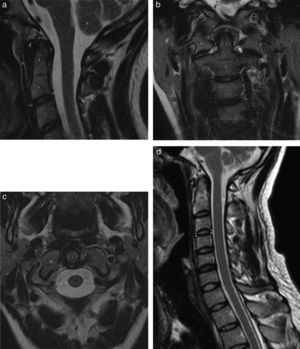

Correlación en plano sagital de RM en secuencia FSE T2 (a) con tomografía computarizada en reconstrucción MPR (b) que demuestra osteoartrosis multinivel, discreta C1-C2 (*) y más grave en la columna cervical baja, especialmente en C4-C5 y C5-C6, osteofitos marginales (flechas), cambios en los platillos (cabezas de flechas negras) y deshidratación discal múltiple (cabezas de flecha blanca). Nótese la dificultad para diferenciar en la resonancia magnética el componente discal de los osteofitos comparando con la correspondiente imagen de TCMD.

Hiperostosis idiopática difusa (DISH). Imagen potenciada en T2 (a) y potenciada en T1 (b) en plano sagital donde se visualiza calcificación del LLA(1), LLP (2) y ligamento interespinoso (flecha), así como una importante mielopatía., y tomografía computarizada multidetector de reconstrucción sagital (c).